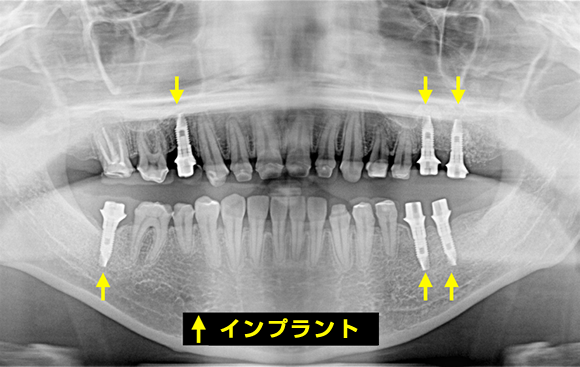

このような審美治療を行い、美しい歯を目指しますが、実は歯茎の上に見えている歯の美しさだけでは、本質的に美しいとは言えないと、私たちは考えています。歯の根元が並行でなく、バラバラに生えてしまっていると、表面を美しく整えても、経年とともに口元の美しさが崩れてしまう上、歯周病のリスクも残ったままです。

当院では、精密な検査によって、患者様の本質的な歯並びまで把握した上で、必要な方には矯正治療をおすすめしています。